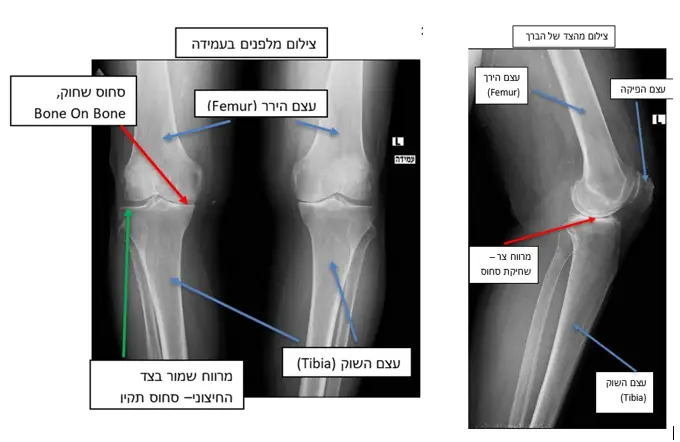

כדי להבין טוב יותר את מבנה המפרק, הנה צילומי רנטגן של הברכיים במנח עמידה באחד ממטופלי:

בין העצמות מצויה רקמת סחוס (בצילום הרנטגן אלה המרווחים הצרים המסומנים בחץ ירוק). זוהי רקמה לבנה, גמישה וחלקה, המאפשרת תנועה חלקה של עצם הירך על עצם השוק. כאשר רקמת הסחוס נשחקת, קיים חיכוך ישיר בין העצמות, דבר המוביל לכאב ולהגבלה בתנועת מפרק הברך (ניתן לראות זאת בחלקי הצילום המסומנים בחץ אדום). בשפת המנתחים מצב זה מכונה Bone On Bone.

הטיפול נקבע על-פי דרגת השחיקה ועוצמת הכאב. לא כל שחיקה גורמת לאובדן מלא של העצם (כפי שמודגם בצילומי הרנטגן). מדובר במצב קיצוני, ולמעשה אצל רוב המטופלים תופיע שחיקה קלה עד בינונית.